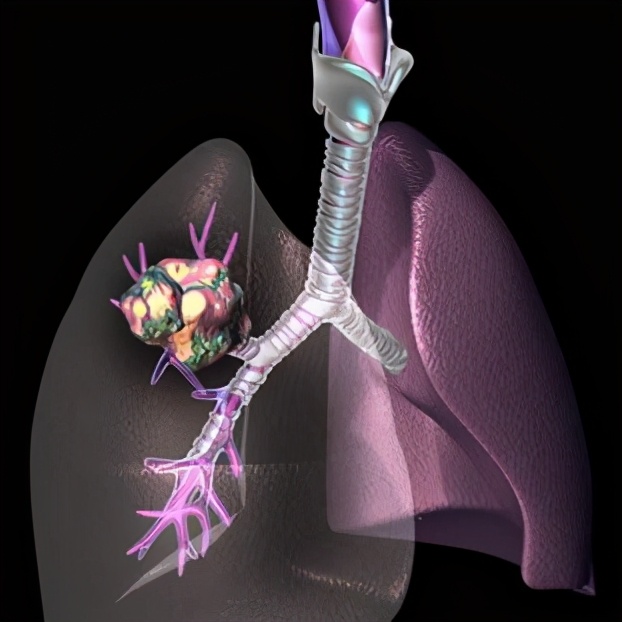

导语:特发性急性嗜酸性粒细胞性肺炎(AEP)通常表现为急性发热性疾病(持续时间短于4周,通常少于7日)、干咳和逐渐加重的呼吸困难。其他伴随症状和体征可能包括不适、肌痛、盗汗和胸膜炎性胸痛。AEP最常与开始吸烟或戒烟后又恢复吸烟有关。大量吸入烟雾、细沙土和粉尘也与AEP有关。在小部分患者中,肺组织病理学检查显示广泛异常伴肺间质和肺泡腔内显著的嗜酸性粒细胞浸润,以及急性和/或机化性弥漫性肺泡损伤(DAD),但不存在肉芽肿或出血。

AEP发病之初,胸片可能仅有轻微的网状影或磨玻璃影,常可见Kerley B线。随着疾病进展,可出现双肺弥漫性混合的磨玻璃影和网状影。就诊时也可见单独的磨玻璃影(约25%的病例)或网状影(约25%)。AEP的阴影呈弥漫性分布,而CEP的阴影通常局限于肺外周。少量胸腔积液很常见(见于多达70%的患者),常为双侧。